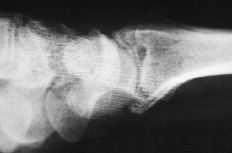

Figura 1. Artroplastia de silicona en semilunar.